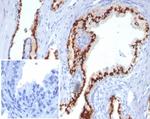

Prostein (p501S)/Solute Carrier Family 45 Member 3 (SLC45A3) Antibody in Immunohistochemistry (Paraffin) (IHC (P))

Prostein (p501S)/Solute Carrier Family 45 Member 3 (SLC45A3) Antibody (85414-RBM1-P1ABX) in IHC (P)

Formalin-fixed, paraffin-embedded human prostate carcinoma stained with Protein (p501S) Recombinant Rabbit Monoclonal Antibody (ZR9). HIER: Tris/EDTA, pH9.0, 45 min. 2 °: HRP-polymer, 30 min. DAB, 5 min. {{ $ctrl.currentElement.advancedVerification.fullName }} 验证信息 View more